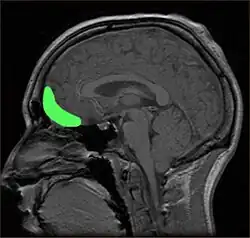

Há uma série de testes neuropsicológicos disponíveis para esclarecer a natureza e a extensão da disfunção do lobo frontal. Por exemplo, a formação de conceitos e a capacidade de mudar conjuntos mentais podem ser medidas com o Teste Wisconsin de Classificação de Cartas, e o planejamento pode ser avaliado com o subteste Labirintos do WISC [en].[3] A demência frontotemporal aparece como atrofia do córtex frontal na ressonância magnética.[21] O comprometimento frontal devido a lesões na cabeça, tumores ou doença cerebrovascular também aparecerá na imagem cerebral.[4]